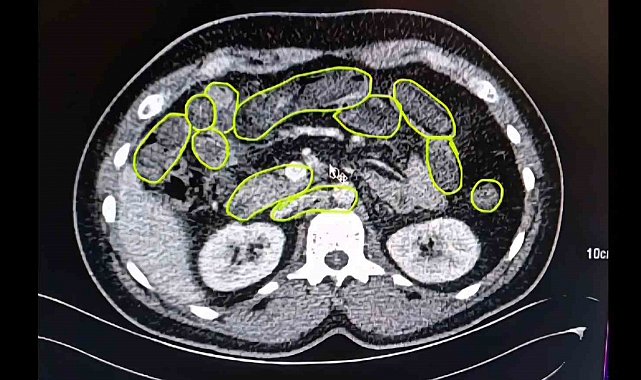

Şüphelilerin Kayseri Şehir Hastanesinde iç beden muayenesine alınırken, mide ve bağırsaklarında da çok miktarda kapsül şeklinde uyuşturucu olduğu değerlendirilen yabancı maddeler tespit edildi.

Mide ve bağırsaklarından uyuşturucu çıktı